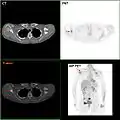

- F-18 FDG PET/CT: A breast cancer metastasis to the right scapula